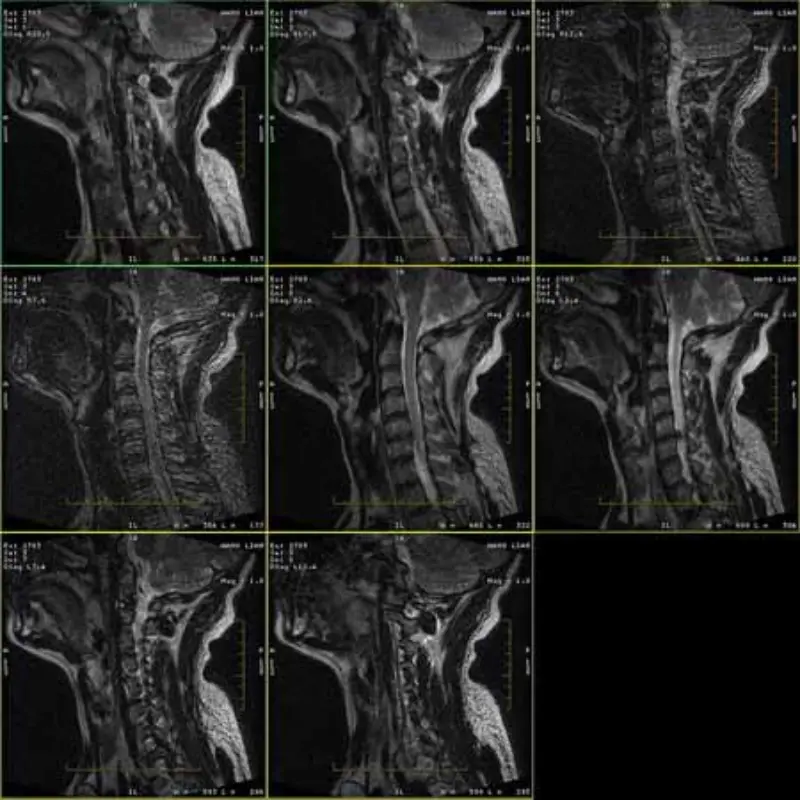

Сликите на протоколите FRFSE и GRE имаат дух, а понекогаш и слики со низок SNR се појавуваат во една серија. Но, сликите од протоколот SE се нормални.

Ве молиме погледнете прикачете слики.